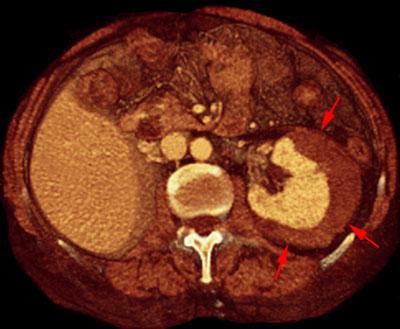

Hematoma subcapsular y perirrenal